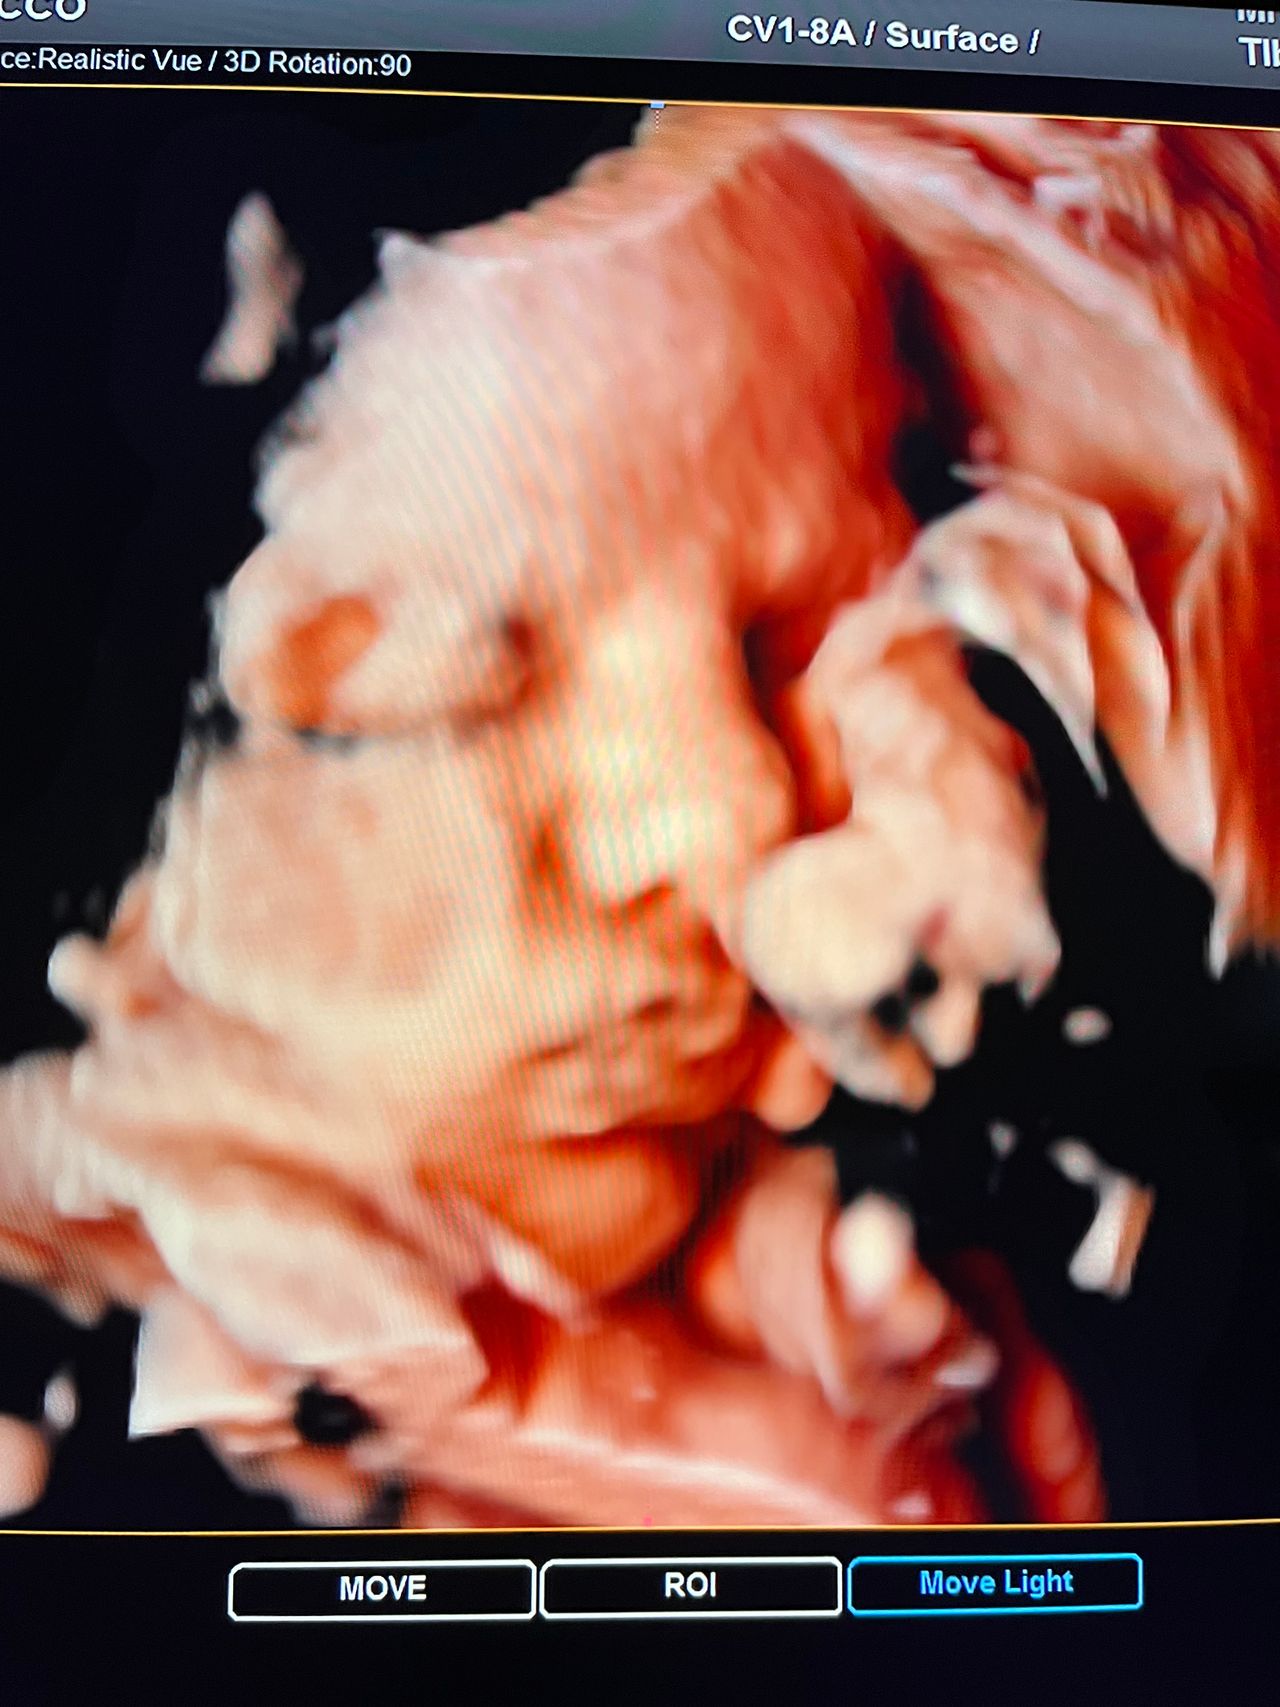

Attualmente lavoro come Dirigente medico nella SC di Ostetricia e Ginecologia dell'Ospedale Michele e Pietro Ferrero di Verduno, mi occupo prevalentemente di screening prenatale, ecografia ostetrica del I trimestre( misurazione translucenza nucale,NT), ecografia morfologica del II trimestre, ambulatorio pregresso taglio cesareo, ecografia ostetrica 3D. Seguo le gravidanze fisiologiche e quelle ad alto rischio , presto servizio in sala parto. Eseguo visite ginecologiche di I-II livello in regime ambulatoriale, counseling contraccettivo ed eventuale prescrizione pillola, inserimento spirale (IUD), dispositivo sottocutaneo (Nexplanon).

Foto e video